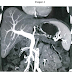

Mujer de 65 años. Consulta por síndrome constitucional asociado a dolor abdominal epigástrico progresivo irradiado a espalda, de dos meses de evolución. El diagnóstico de sospecha de adenocarcinoma de páncreas se confirma por biopsia guiada por ecoendoscopia. Se realiza TC de abdomen tras administración de contraste intravenoso para valoración de estructuras vasculares próximas al tumor pancreático, a fin de establecer su posible afectación. (ver imagen).

¿Qué estructura vascular está ausente, trombosada por infiltración tumoral, condicionando circulación colateral en la pared gástrica?